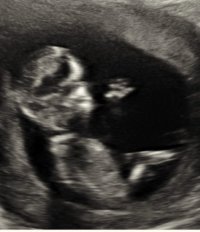

Var på TUL i dag 13+3. Hun mente det kunne se ut som jente men ville ikke bekrefte noe. Hva tror dere? :)

Jeg har ikke peiling på sånt! Men jeg synes det ser ut som en gutt, eller.. jeg vet ikke:smiley-ashamed004

Du kan evt spør i en gruppe på fb :Heartred